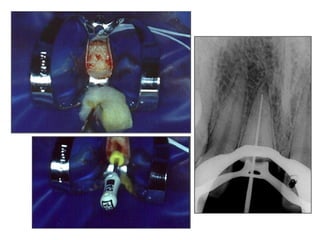

Após a formação do ápice foi realizado uma gengivoplastia para isolamento absoluto e tratamento endodôntico.

Isolamento absoluto

Odontometria e obturação do canal radicular

Após a formaçãodo ápice foi realizado uma gengivoplastia para isolamento absoluto e tratamento endodôntico.

Odontometria e obturaçãodo canal radicular